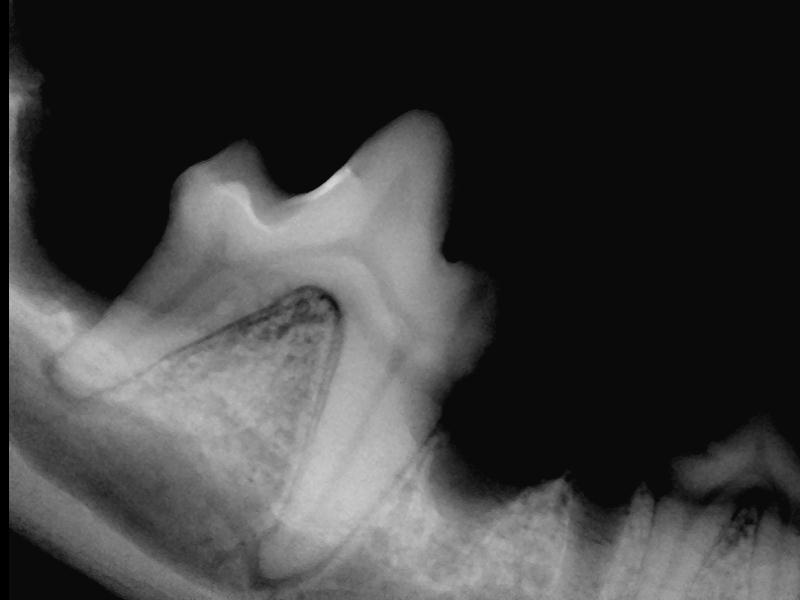

Via tandrøntgen ses eventuelle rod problemer, som ikke ville være opdaget ved blot at se på selve tanden.